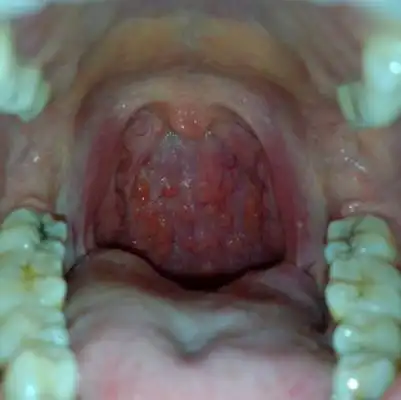

咽喉良性肿瘤